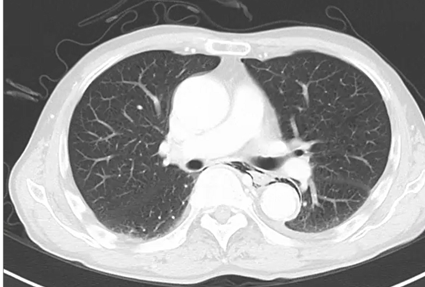

54歳女性。既往に気管支喘息とアレルギー性鼻炎がある。 3ヵ月にわたる湿性咳嗽と呼吸困難を認め救急外来受診となった。 発熱と悪寒、寝汗、体重減少(9㎏)を伴って…